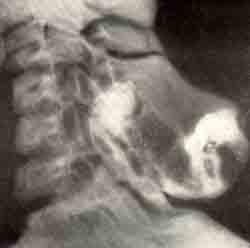

Юношеский костно-хрящевой экзостоз остистого отростка VII шейного позвонка при множественной экзостозной хондродисплазии у девочки 9 лет: а — фотография больной; б — рентгенограмма позвоночника.

Юношеский костно-хрящевой экзостоз